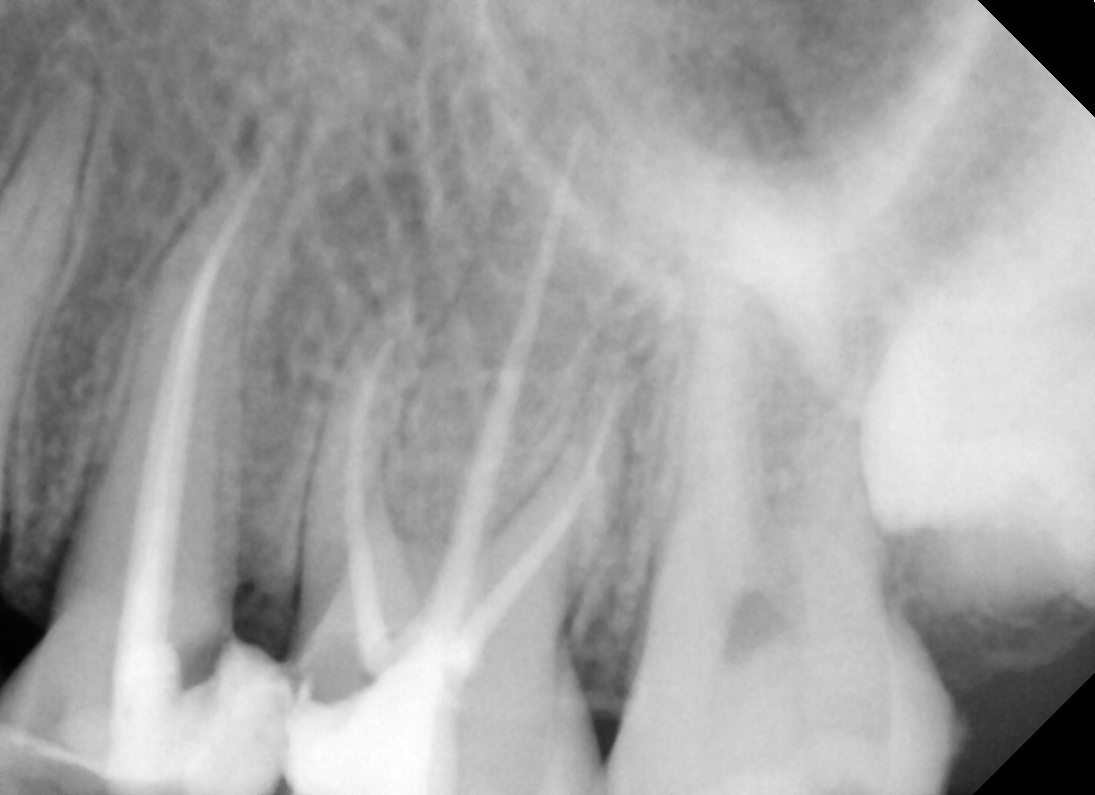

• A diagnosis is made for the tooth with percussion, palpation and cold tests and an x-ray.

• Measurements of the length of the root canal is noted and take x-rays to confirm the length. Ensuring that the entire length of the root canal is cleaned.

Gallery